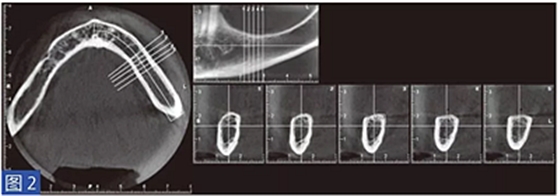

對(duì)萎縮的牙弓進(jìn)行了初步的錐形計(jì)算機(jī)斷層(CBCT)掃描,以評(píng)估硬組織的三維形態(tài)。根據(jù)這些數(shù)據(jù)用特殊的環(huán)氧基熱固型光敏樹(shù)脂(3DIEMME) 打印頜骨模型。這個(gè)環(huán)氧樹(shù)脂的解剖形態(tài)模型用于作為骨重建手術(shù)術(shù)前設(shè)計(jì)的框架。

在整個(gè)手術(shù)過(guò)程中以及術(shù)后12 個(gè)月都要評(píng)估并發(fā)癥的發(fā)生。在術(shù)后12 個(gè)月,患者都要通過(guò)視覺(jué)模擬量表(VAS)對(duì)手術(shù)的滿意度從0(非常不滿意)到10(非常滿意)進(jìn)行評(píng)估。這些問(wèn)題針對(duì)對(duì)于治療過(guò)程的主觀評(píng)價(jià)。圖1-12 顯示了兩個(gè)典型病例的手術(shù)。

圖2:病例1. 術(shù)前左下頜骨CBCT 掃描結(jié)果。